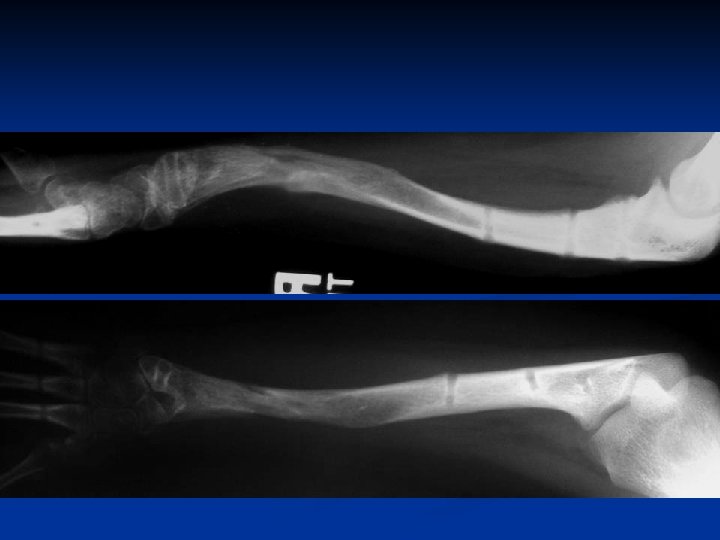

Lengthening of the Forearm for Radial Clubhand

Strategy Dependent on age at presentation Age 6 10 years Two lengthenings

• Before age 10 years st 1 lengthening 4 -6 cm • After age 10 years nd 2 lengthening 6 -8 cm

before after normal Before vs After 1 st Lengthening vs Normal side

preop st lengthening 1 st 1 lengthening: 7 cm 8 cm 2 ndlengthening: lengthening 2 nd 10 cm Total length gain 18 cm

7 y. o. girl with rch and partial growth arrest 1 st Lengthening: 6 cm

before after

2 nd Lengthening

Strategy Dependent on age at presentation • Age 11 20+ years one lengthening 8 12 cm